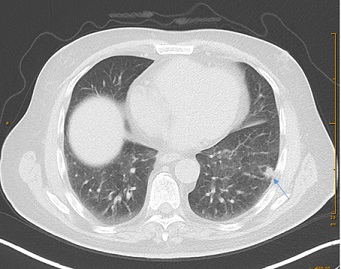

At the age of 66 the patient was diagnosed with a 4 cm pancreas tail tumor with synchronous liver metastasis in Positron-Emissions-Tomographie/Computer Tomographie (PET/CT) in 2014 (Figure 1A&1B). Initial CA 19-9 was 181 kU/l (Figure 2) in June 2014. The patient was oligosymptomatic, he had spine pain, fatigue and no significant weight loss. At the age of 65, he had some kind of belly pain and received a CT of the abdomen in 2013, however his pancreas and other organs were clean. In retrospective the cancer was already seen on that CT without liver metastasis (Figure 3). His risk factor for pancreas carcinoma were smoking, regular alcohol consumption and a positive family history for cancer. He was a smoker (30 pack-years (PY)) and quit in 1982. Despite the presence of liver metastasis the patient wished to be operated on. Preoperative the patient received pseudo-neoadjuvant chemotherapy mFOLFIRINOX (15 cycles) from May 2014 until January 2015.  After chemotherapy a regression of the tumor, liver metastasis (Figure 4) and CA 19-9 (Figure 2) was observed. However a new 19 mm metastasis of liver occurred. Despite that fact a successful pancreas tail resection with lymphadenectomy and splenectomy was performed on in April 2015. Based on the histopatology the tumor staging was pT3, G3, L0, V1, Pn1, R0. The morphology of the tumor was poorly differentiated adenosquamous carcinoma and tumor size was 2.5 cm diameter. Radiofrequency Ablation (RFA) of liver metastasis were done in April 2015. One year postoperatively diabetes mellitus type 2 was diagnosed and insulin therapy was started in March 2015.

Figure 1: Axial image from a pre-operativ contrast-enchanced CT scan of the abdomen in our patient with pancreastic tail tumor in (A) and 13 mm liver metastasis close next to draining point of liver veins into vena cava inferior (Segment VII) in (B).